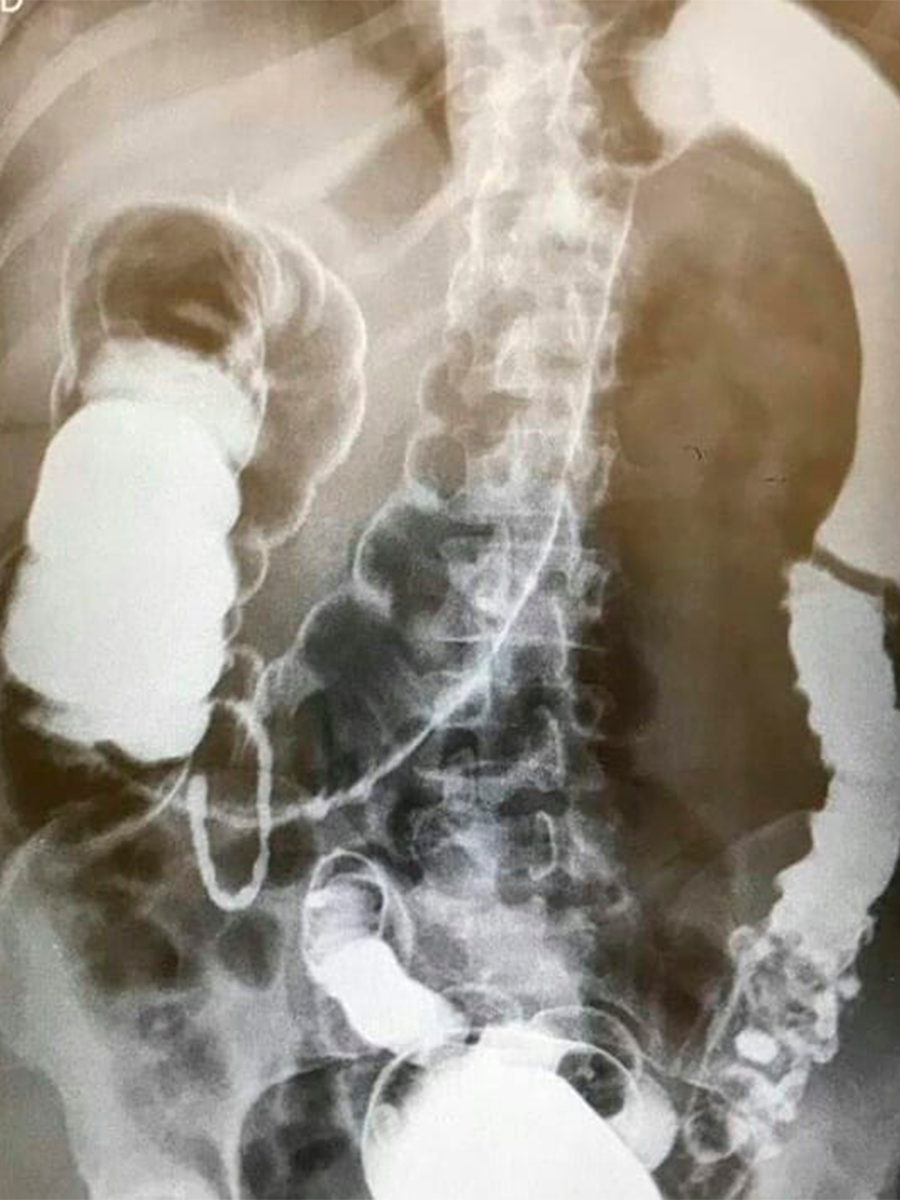

O enema opaco, também conhecido como clister opaco, é um exame radiográfico